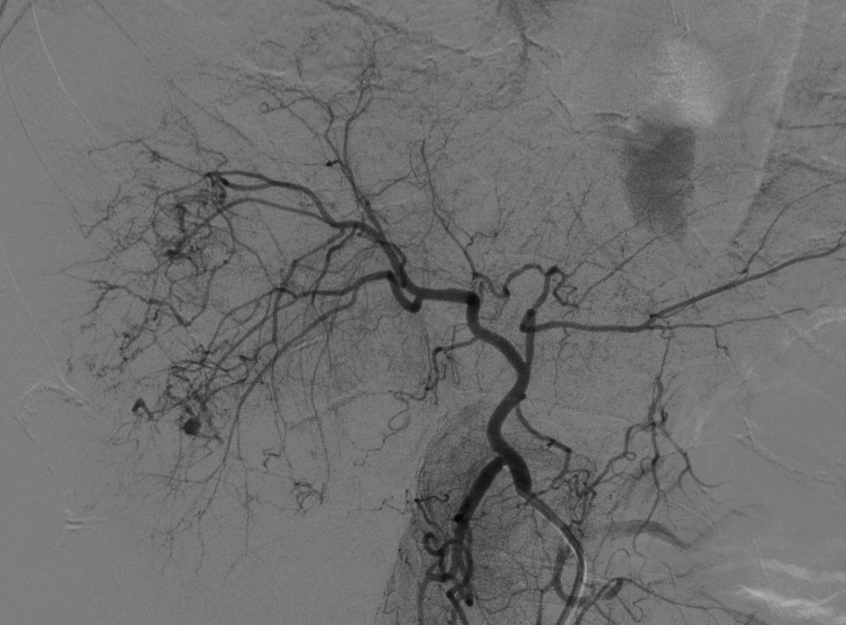

入院后,为患者给予补液,在局部麻醉下行DSA引导下经导管肝肿瘤动脉栓塞术。

手术顺利,术后患者转正重症医学科给予输血、补液、止痛及康复治疗。术后3天,患者复查血,肝功能正常。后续恢复良好,并在短期内出院。

肝癌破裂大出血并失血性休克患者往往病情急、危、重,如果治疗不及时可能短期内死亡。未开展介入治疗的医院对此类患者只能给予输血,补液,急诊手术,在插管全麻下行开腹手术治疗。但开腹手术往往切口长、手术时间长、手术创伤大,麻醉副作用大。可能术后出现肝功能衰竭,再出血,腹腔感染,切口疼痛,切口感染等并发症。介入手术则往往较少出现这些并发症。介入手术只需要在腹股沟穿刺一个2mm的小孔,置入导管到肝动脉,注入栓塞剂栓塞肝肿瘤的动脉,手术创伤小,止血可靠,除肝区疼痛及发热外,较少出现其它并发症,病人舒适度明显提高,而且能早期进食及下地活动,恢复快,能缩短住院时间,具有疗效好且微创的优点。